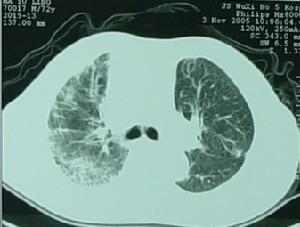

2.復發性細菌性肺炎反覆發作時可以造成支氣管擴張,早期這種支氣管擴張可呈圓柱形並且是可逆鵻的但在多次肺炎發作後由於支氣管損害可發展成靜脈曲張狀或囊性支氣管擴張位於下葉是其特點,感染早期胸片是正常的,在肺底有線狀陰影聚集這時支氣管造影可顯示支氣管擴張當支氣管擴張進鵻一步發展則可呈小囊狀支氣管擴張,用高解析度CT(HRCT)可取代支氣管造影而獲得診斷。